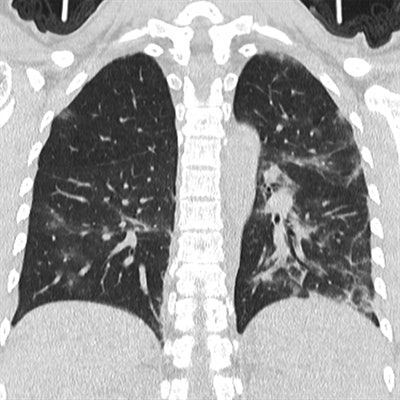

As a whole, the CT scans predominantly displayed ground-glass opacity in the early stage of COVID-19. The CT features evolved into patches of crazy-paving patterns and consolidation as the disease progressed, with lesions showing absorption by the final stage of the disease. Disease distribution was chiefly in the lower lobes, at 96% of all cases; involvement in the upper lobes was present in 52% to 72% of cases.

The researchers additionally used a semiquantitative CT technique to estimate the extent to which abnormalities affected the lungs.

On average, the patients' CT score indicated less than 1% pulmonary involvement during the early stage of the disease. The average amount of involvement gradually increased in correlation with increasing disease progression, from roughly 25% during the progressive stage of the disease to a peak of about 26% to 49% involvement during the final absorption stage.